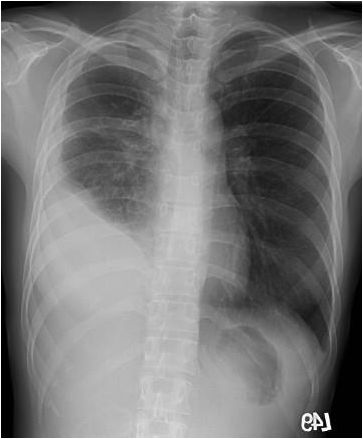

1. 一位37歲女性一個月來呼吸困難逐漸明顯,胸部X光如圖所示,應先採取下列何種處置?

(A) 先抽胸水(30-50ml)送檢 (B) 放引流管將水一次抽完並送檢 (C) 做胸部電腦斷層,看是否有腫瘤 (D) 做肋膜生檢(切片)送病理學檢查 (E) 先試用2-3天的口服利尿劑